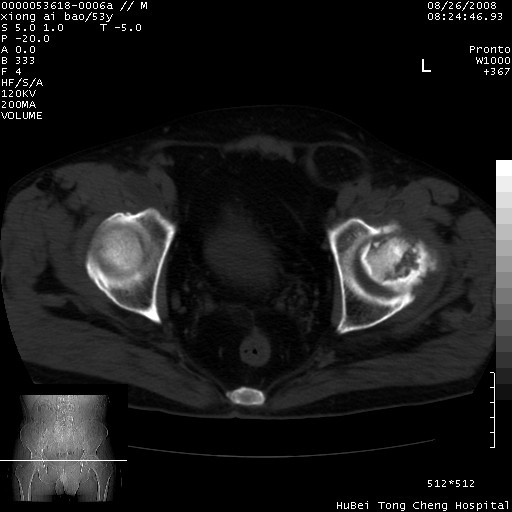

标题: CT15583:M,53Y。请老师指教分析骨盆及其他病变。 [打印本页]

标题: CT15583:M,53Y。请老师指教分析骨盆及其他病变。

股骨头坏死/腹股沟疝。

双侧股骨头无菌坏死,左侧腹股沟斜疝。

非常典型病例,双侧股骨头坏死伴双髋关节周围软组织肿胀,左腹股沟疝。

双侧股骨头坏死伴双髋关节周围软组织肿胀,左腹股沟疝。

双侧骨股头无菌性坏死,左侧腹股沟疝

双侧髋关节肿胀明显,感觉还不能排除结核。

考虑双侧髋关节结核,左侧腹股沟疝